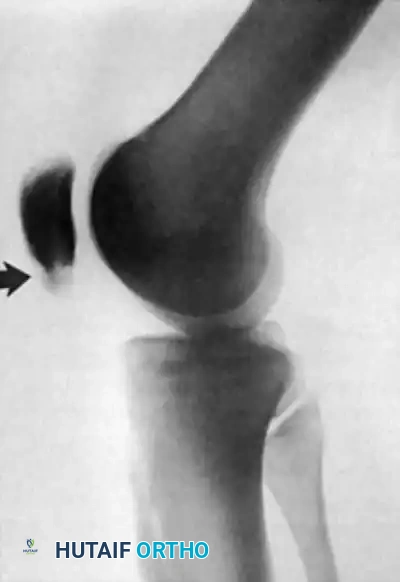

FIGURE 48-28: Stress fracture of the inferior pole of the patella in a collegiate basketball player. The fracture is secured with parallel screws, and a corticocancellous slot graft is placed distally across the fracture site to promote osteosynthesis.